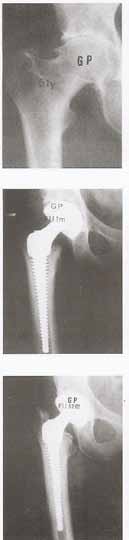

Modular stems have a long history starting with McBride in 1948 that utilized a threaded femoral component and publishing his first account in

JBJS in 1952. This was followed in 1978 by Bousquet and Bornand with the development of a proximal modular stem that featured a proximal body that was attached to a stem via a conical mounting post, with 8 perforations that allowed for select angle orientation for biomechanical restoration. Their design also featured a screw-anchored intramedullary stem design that was coated with AL2O3. Their initial reports were presented in Basel in June 1982 at a symposium on cementless hips and published in Morscher's 1984 book "The Cementless Fixation of Hip Endoprostheses". The BSP Modular stem followed in 1988 and featured a modular collar/neck assembly that was fixed to the stem with a morse taper joint, a saw-tooth macro interlock system (15º rotation per tooth) and a set screw.[18]

The current S-Rom® Stem System represents the fourth generation in the evolution of the Sivash Total Hip Stem since it was introduced in the United States in 1972.[16,22,23]

Sivash began development of his prosthesis in 1956 at the Central Institute for Orthopaedics and Traumatology, Moscow, Russia. By 1967 Sivash had selected titanium alloy for the femoral stem and proximal sleeve and chrome cobalt alloy for his socket bearing and femoral head. A major focus was the design of a constrained socket. The Sivash Total Hip System, introduced by the US Surgical Corporation, never received major clinical or market success, partially due to the difficulty of the surgical technique, and positioning of this constrained device.